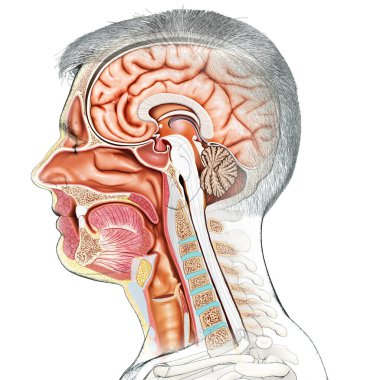

The arterial blood supply to the neck (carotids and vertebral arteries).

İnsanBaşıkanİlaçyüzboğazıBoyunresim çalışmasıprofilNormalbeyinarterkarotidKan damarıKan dolaşımıİnsan AnatomisiSerebral kan dolaşımıvaskülarizasyonsubclavian arteryortak Karotis arterbrachiocephalic Arteryel gövdeVertebral arterfacial arteryserebral artercervical arterytemporal arterydahili şah damarıharici şah damarıdeep cervical arteryBenzer İçerikler